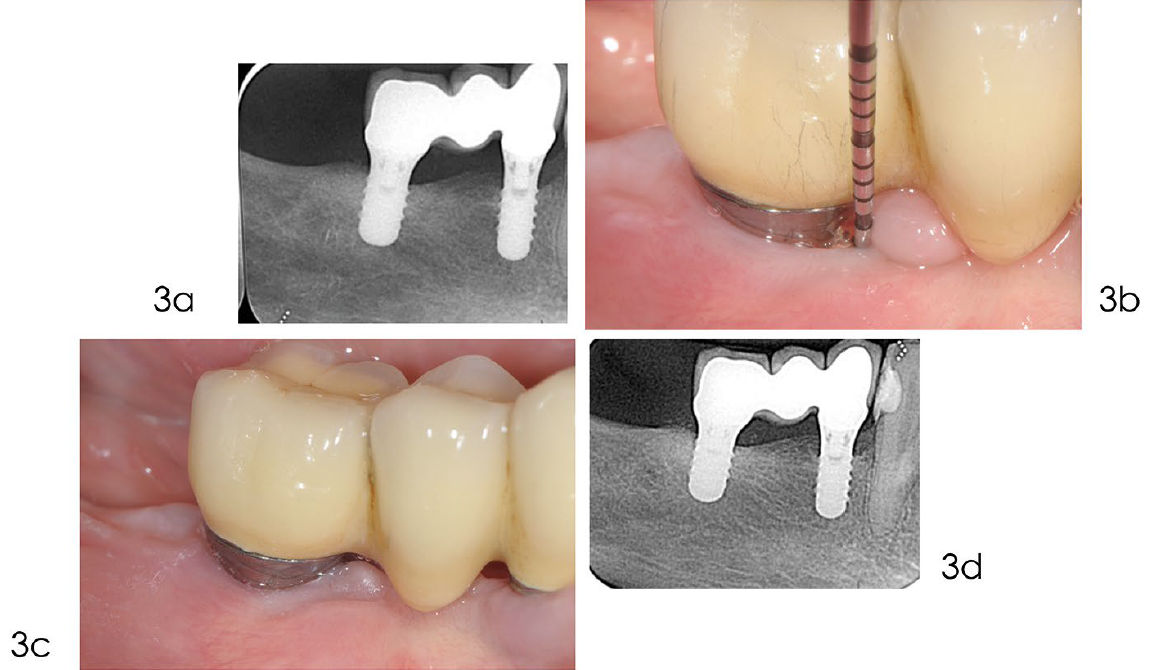

Фото 3. Динамическое наблюдение (поддерживающая терапия)

a) Рентгенограмма, выполненная в мае 2019 года, демонстрирует полное заполнение дефекта костью. b) После хирургического лечения пациенту была назначена индивидуализированная программа поддерживающего ухода, включающая гигиену полости рта, удаление биоплёнки и контроль факторов риска. c) Клиническое изображение от ноября 2021 года показывает здоровые ткани вокруг имплантата. Зондирование выявляет неглубокие карманы и отсутствие кровоточивости. d) Рентгенограмма, выполненная в марте 2023 года, через 16 лет после установки имплантата, демонстрирует оптимальный уровень межзубной кости